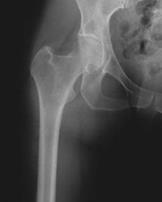

¿Qué es un reemplazo de cadera?

Un reemplazo de cadera es una cirugía que extrae la bola artrítica del fémur superior (hueso del muslo) junto con hueso y cartílago que se han dañado de la cavidad de la cadera. La bola se reemplaza con un implante de metal fijado de forma segura dentro del fémur, y la cavidad se recubre con una inserción de plástico o metal, a menudo con el apoyo de una cubierta de metal. Juntos, estos componentes crean una articulación suave y funcional que alivia el dolor y restaura la movilidad.